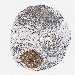

BRCA TCGA BRCA VALIDATION PROTEIN EXPRESSION